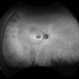

- toxic maculopathy

Clarus 700 - Description

- A 50-year-old woman with a 15 year history of pentosan polysulfate treatment for interstitial cystitis.